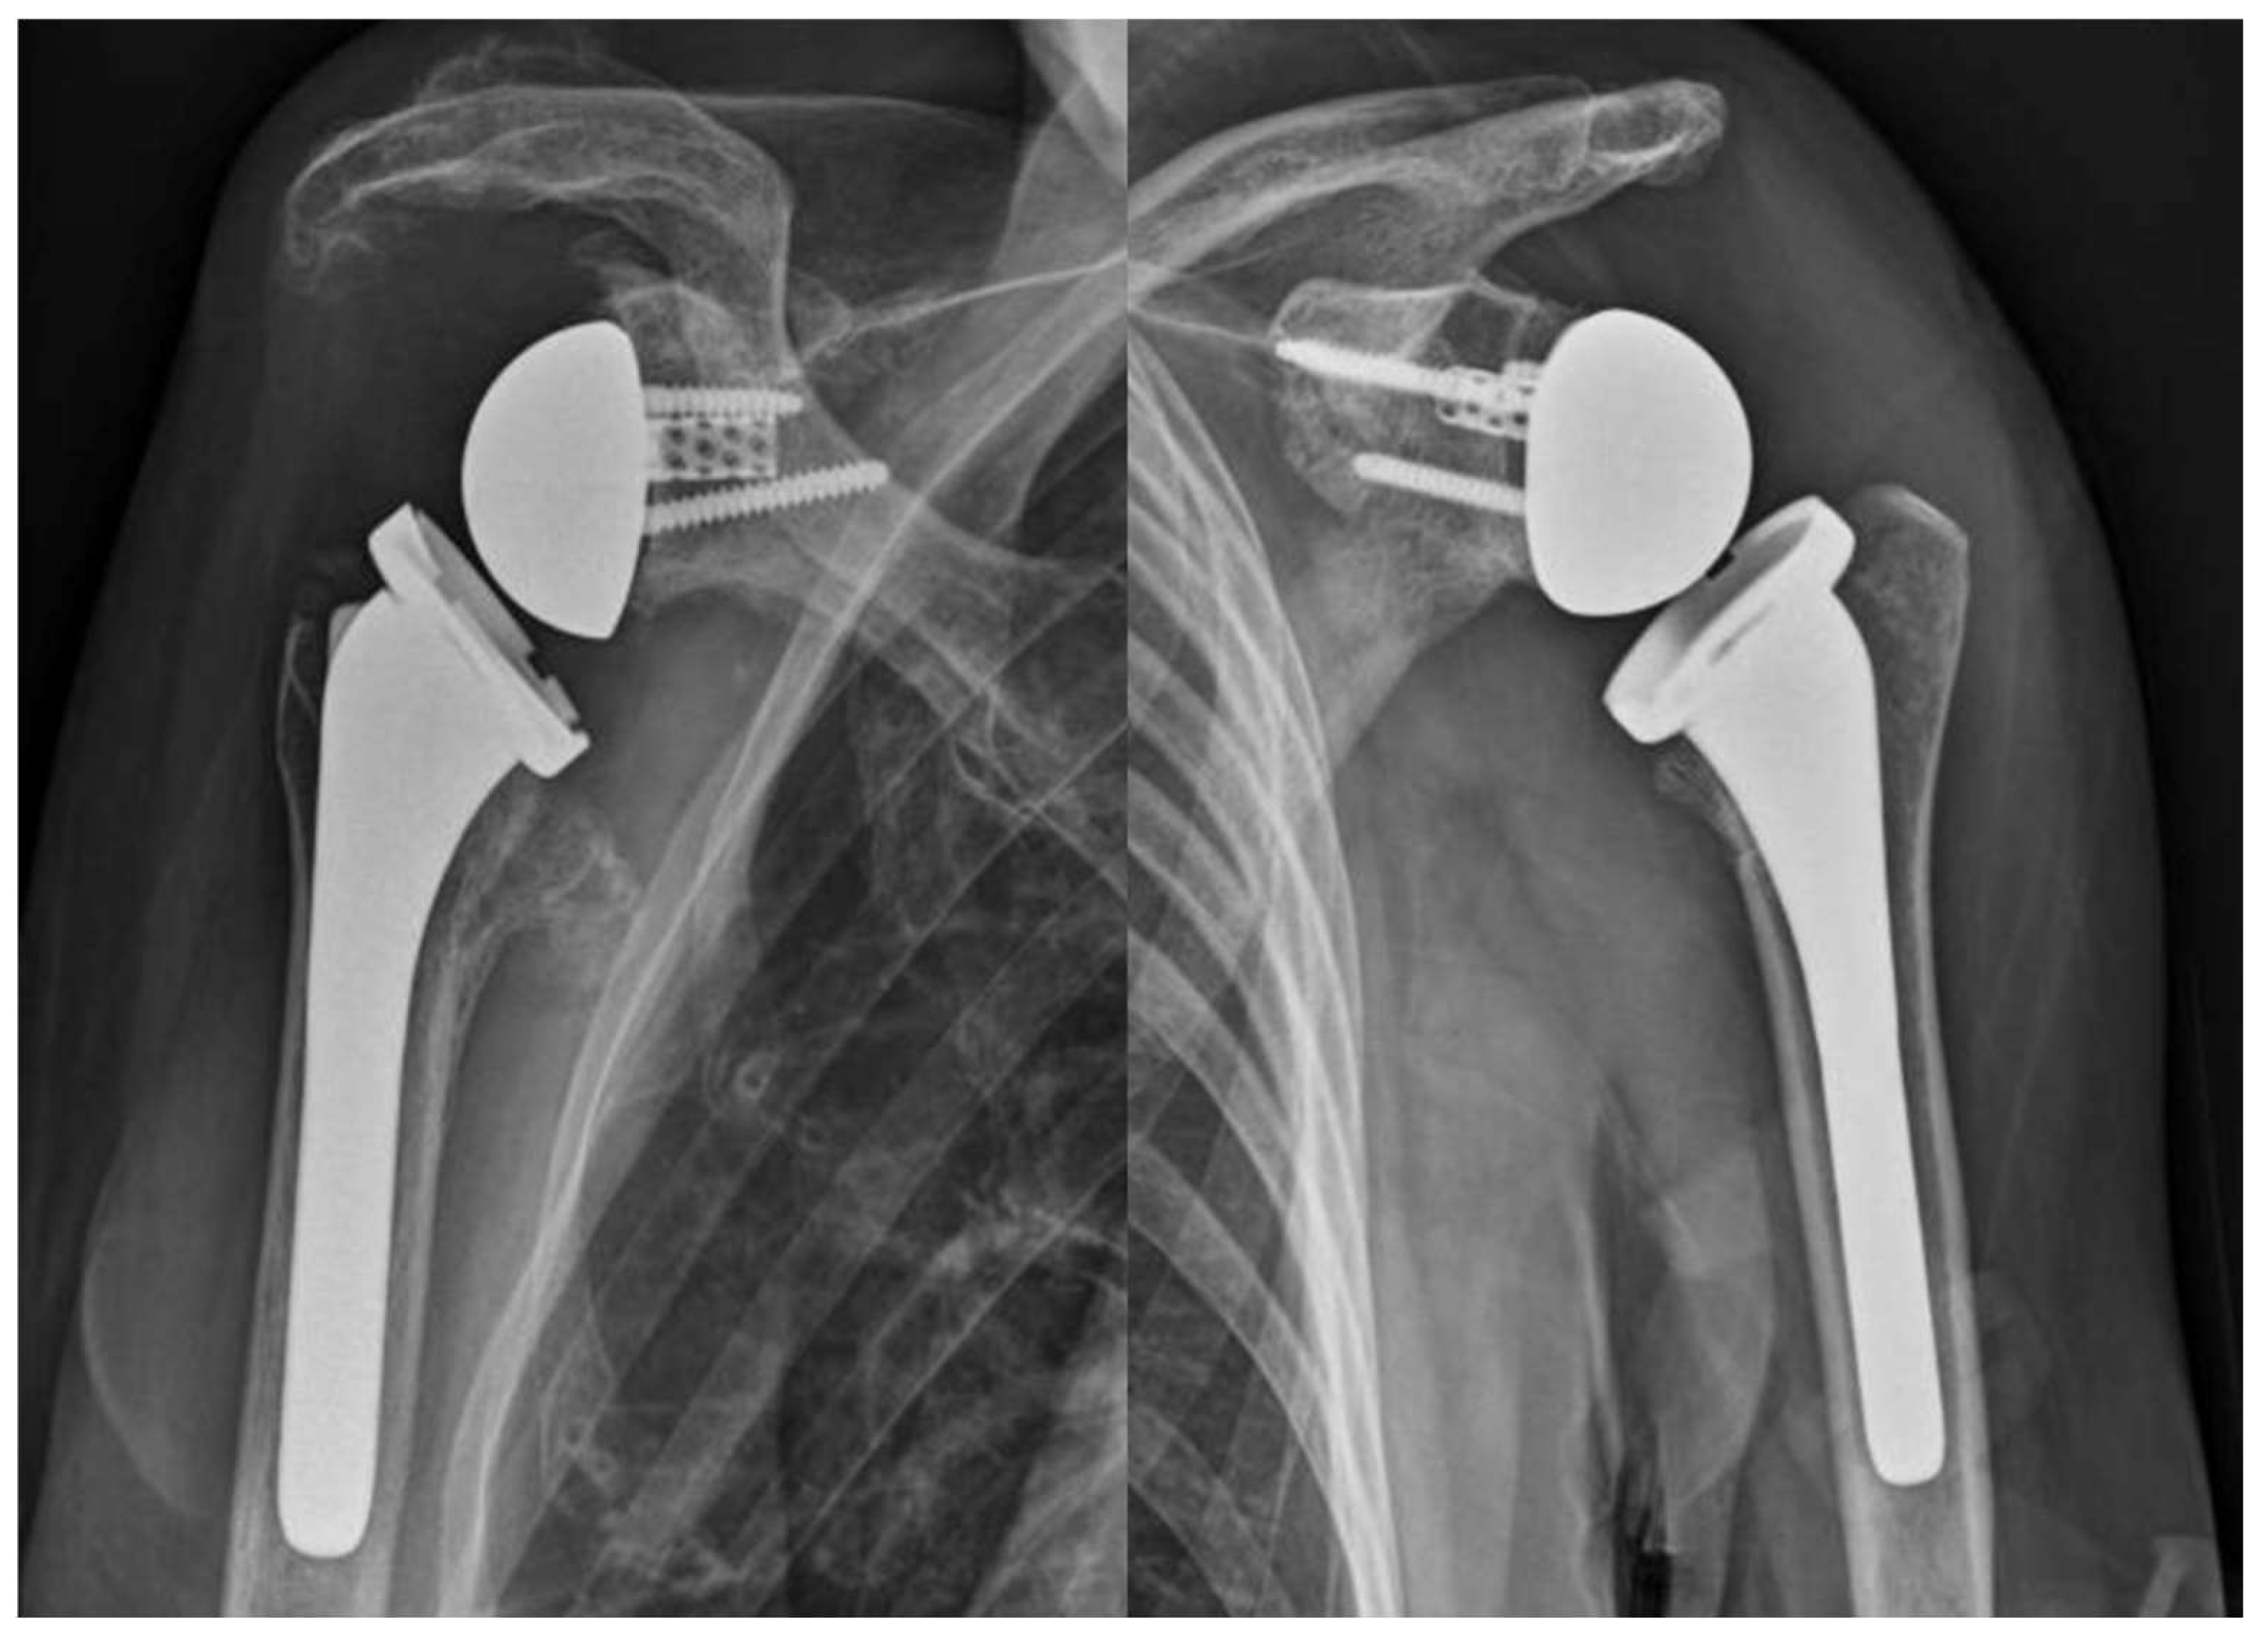

At the final follow-up radiographic evaluation, no areas of radiolucency, peri-implant bone resorption, or device mobilization were detected (Figure 3).

Figure 3. X-rays at the final follow-up.